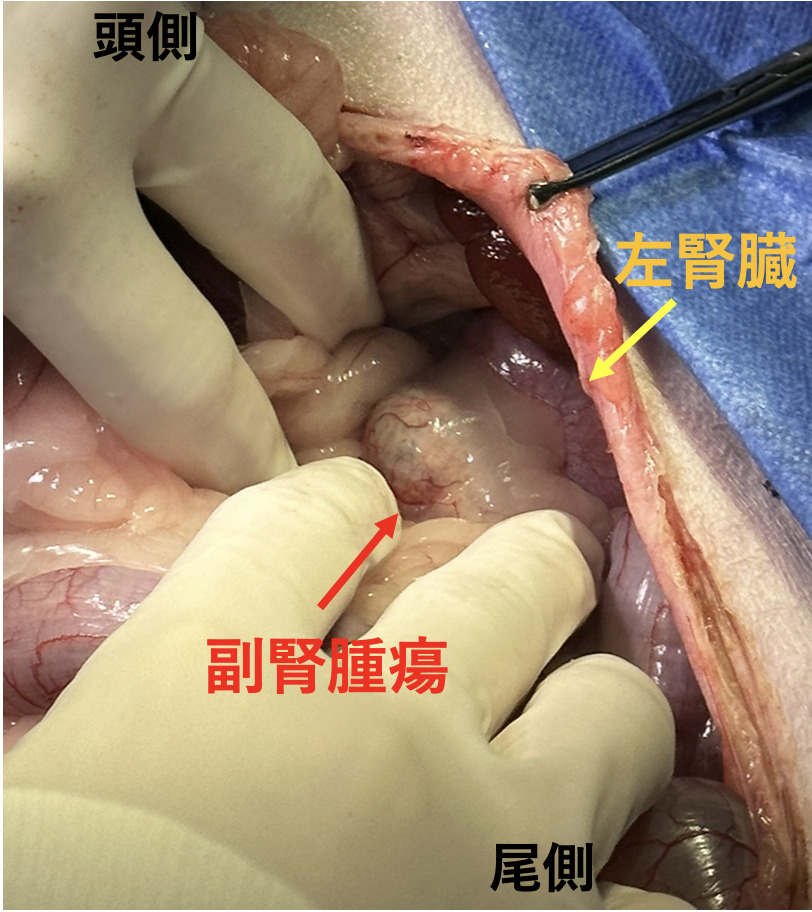

朝倉書店『内科学』(第12版)デジタル付録, 副腎腫瘍・副腎腺腫摘出 - 横浜みどり動物医療センター しょう,

副腎腫瘍・副腎腺腫摘出 - 横浜みどり動物医療センター しょう, 20443T,

腎盂・尿管・膀胱癌 第2版(腫瘍病理鑑別診断アトラス) 宮居 弘輔, 副腎腫瘍・副腎腺腫摘出 - 横浜みどり動物医療センター しょう,

副腎腫瘍・副腎腺腫摘出 - 横浜みどり動物医療センター しょう, 腎盂・尿管・膀胱癌 第2版(腫瘍病理鑑別診断アトラス) 宮居 弘輔